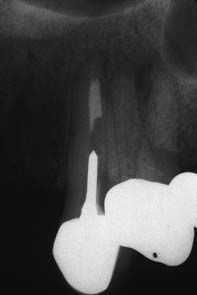

A post that has fractured within the root canal cannot be removed with a post puller or forceps. The post can be drilled out, but great care is needed to avoid perforation. The technique is best limited to relatively short fractured posts (Fig. 12-48).

Fig. 12-48 Post removal by high-speed bur. A, Preoperative radiograph of the right maxillary lateral incisor, in which both the crown and part of a post have been fractured off. A portion of the Kurer-type, parallel-sided, threaded post remains within the canal. B, Because of the large diameter of the post and its position within the canal, a high-speed handpiece was chosen to drill it out. C, Radiograph to verify the correct orientation of the bur’s progress inside the canal. With this method of post removal, the operator must be extremely careful not to let the high-speed bur contact the canal wall, which would seriously compromise tooth structure. D, Radiograph of the incisor after post removal and re-treatment.

(Courtesy of Dr. D. A. Miller.)